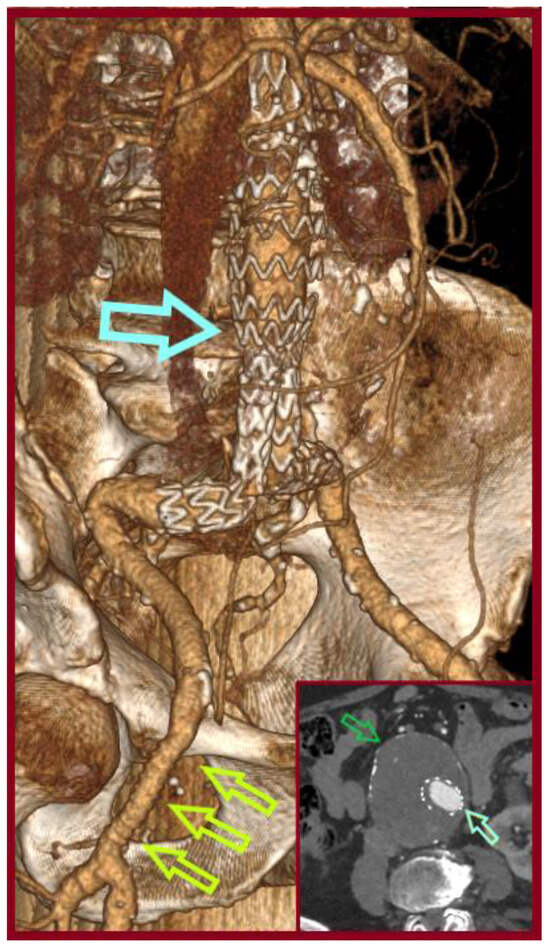

Simultaneous Endovascular Abdominal Aortic Aneurysm Repair and Open Repair of Common Femoral Artery Aneurysm: Short Case Series and Current Review

Background: Common femoral artery aneurysms are rare and are usually associated with aneurysms at other sites, mainly the aorta, iliac, popliteal, superficial femoral, and profunda femoral artery. This combination poses the challenge of synchronous repair for clinically relevant aneurysms. Although endovascular abdominal aortic [...] Read more.

Background: Common femoral artery aneurysms are rare and are usually associated with aneurysms at other sites, mainly the aorta, iliac, popliteal, superficial femoral, and profunda femoral artery. This combination poses the challenge of synchronous repair for clinically relevant aneurysms. Although endovascular abdominal aortic aneurysm repair is the main type of treatment for abdominal aortic aneurysms nowadays, this is not true for common femoral aneurysms, where open repair remains the gold standard. These two distinct operations could be combined in a one-stage procedure when aortoiliac and common femoral aneurysms present simultaneously. This approach potentially saves time and costs, without increasing complications. Methods: A retrospective search was conducted in the Vascular Surgery Department database of a tertiary referral center for vascular surgery, covering procedures from January 2005 to May 2025. Patients were included if they had undergone simultaneous endovascular abdominal aortic aneurysm repair and open repair of a common femoral artery aneurysm. Clinical records, operative details, imaging studies, and follow-up data were reviewed. We additionally provide a literature review regarding this approach. This review additionally incorporates the current knowledge regarding the treatment of common femoral artery aneurysms. Results: Out of 668 endovascular abdominal aortic aneurysm repair procedures, three patients (0.45%) were identified. These three patients were among five patients who were treated for true common femoral artery aneurysm by open repair in the same time interval. All of the patients are currently in good condition without late complications. One patient, who had not performed any follow-up imaging, was diagnosed with large aneurysms at other sites, 10 years later. Conclusions: The combined one-stage endovascular abdominal aortic repair and open repair of a common femoral artery aneurysm by interposition grafting is technically a simple approach that led to satisfactory outcomes. Full article

Show Figures

Figure 1